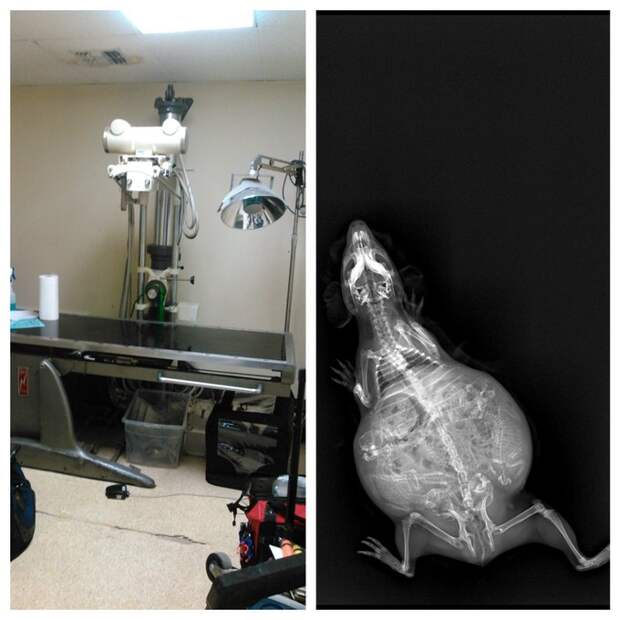

Беременная морская свинка.

Еще одна беременная морская свинка.